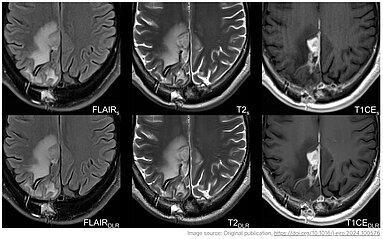

The study conducted by Heidelberg University Hospital investigates the use of diffusion-weighted MRI (DWI) to predict early treatment outcomes in patients with advanced lung adenocarcinoma. The…